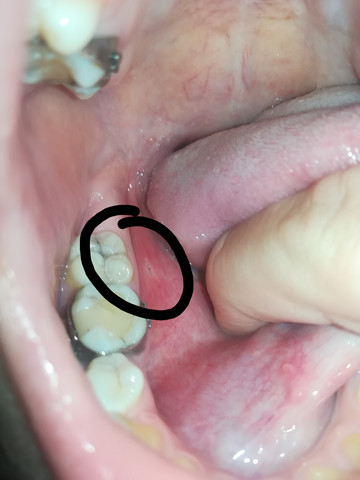

Ja das kann dauern. Risse in der Zunge als Symptom der Krankheit In der Medizin nennt man Risse in der Sprache Glossalgia. Oftmals stehen Risse in der Zunge damit in Zusammenhang dass der Betroffene an einem Flüssigkeitsmangel leidet.

In erster Linie gilt es eine rissige Zunge erst einmal mit einfachen Hausmitteln zu behandeln. Wenn in der Zunge des Patienten Risse. Risse können Nahrung ansammeln was zu Irritationen dem Auftreten kleiner Geschwüre führen kann.

Medikamente die die Heilung von Rissen in der Zunge fördern. Risse in der Zunge sind in der Regel harmlos und heilen innerhalb weniger Tage selbstständig aus.